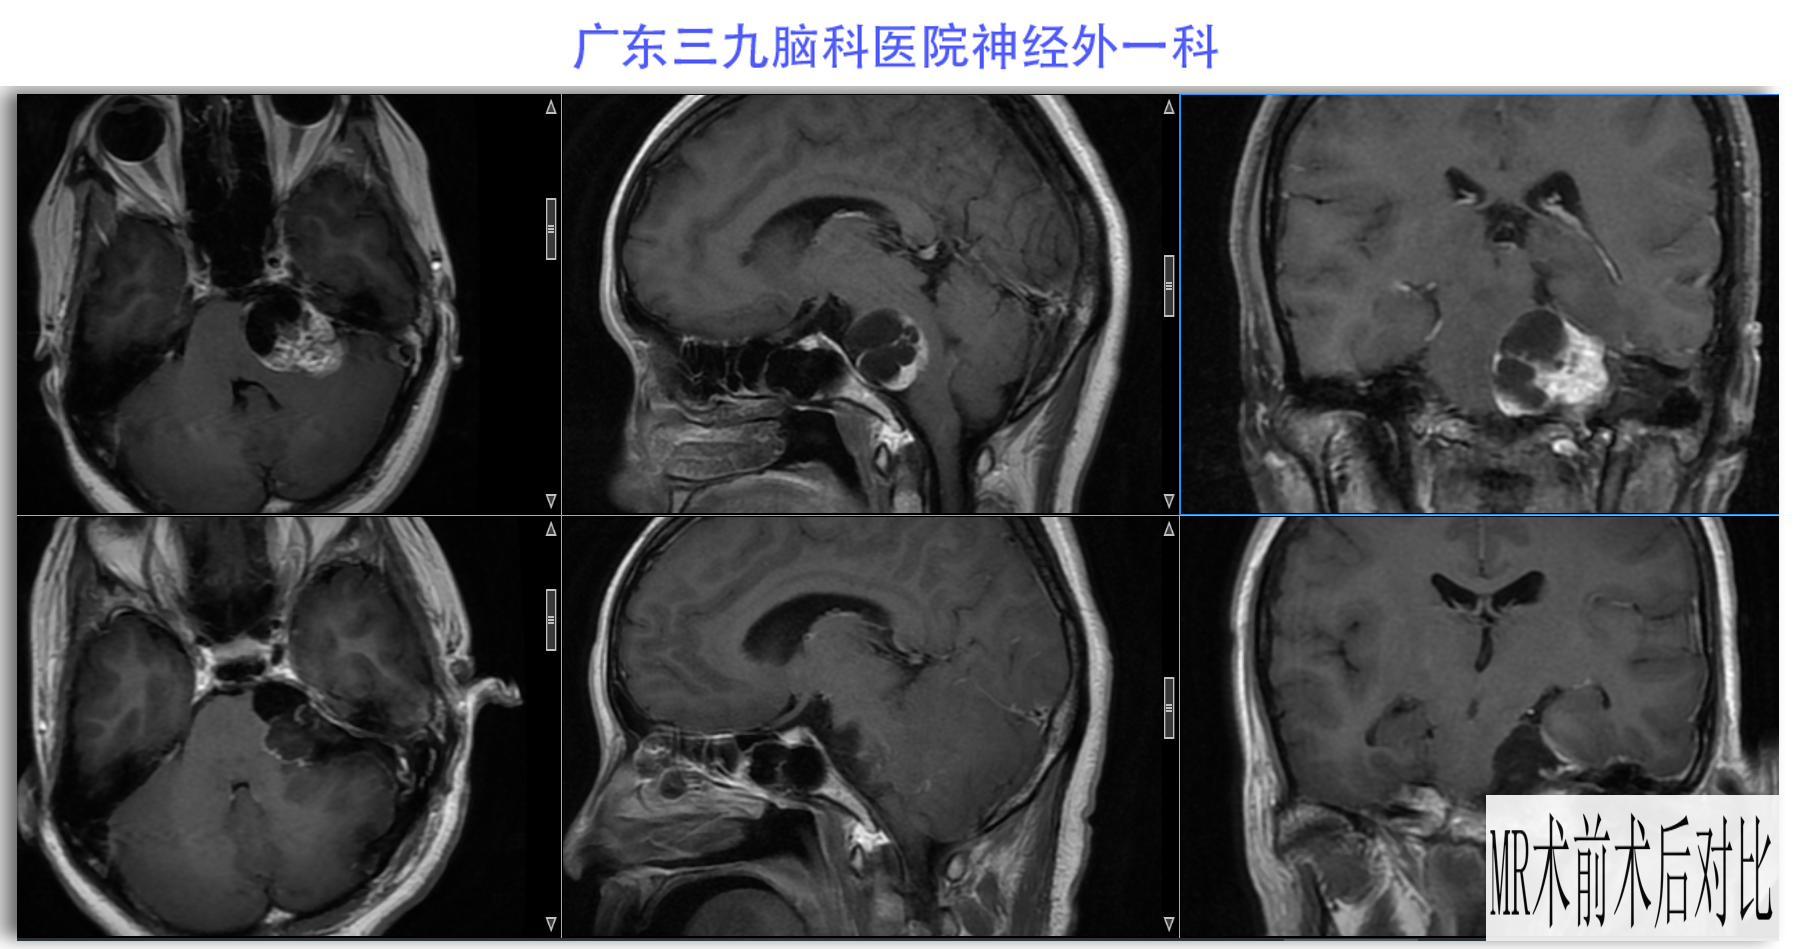

陈某某,女,41岁,因“左侧面部麻木3月余,吞咽困难半月余”于2024-02-17入院。患者3个月前出现左侧面部麻木,偶尔伴有头晕和左侧流泪,但没有听力下降或耳鸣。同时,患者也出现肢体乏力和行走不稳,但未接受任何治疗。半个月前,患者发现吞咽硬质食物稍有困难,同时左侧面部麻木加重。因此,前往当地医院就诊,并进行头颅MR检查,结果显示左侧CPA区存在占位性病变。为了进一步治疗,患者转诊至我院就医。术前检查显示:左侧角膜反射减弱,左侧鼻唇沟略微变浅,伸舌稍微右偏,咽反射迟钝。门诊诊断为“左侧巨大听神经瘤”,收治至我科进行住院治疗。手术过程顺利,术后患者恢复良好,面部轻度瘫痪与术前相同。术后病理检查结果确认为听神经瘤。